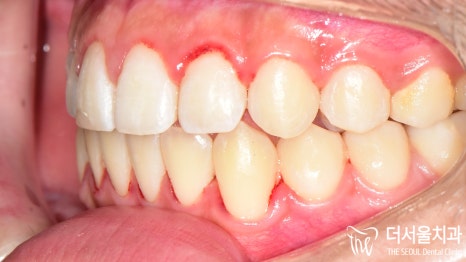

이와 더불어 톡 튀어나와 있는

토끼 이빨이 관찰되고 있는데요.

측면 세팔로 사진에서 볼 수 있듯이

돌출감이 꽤 느껴지고 있었습니다.

전과는 달리 벌어졌던 이 사이도

긴밀하게 붙어 있는 것이 확인되었으며

툭 튀어나와 있던 돌출입도 개선이 되었습니다.